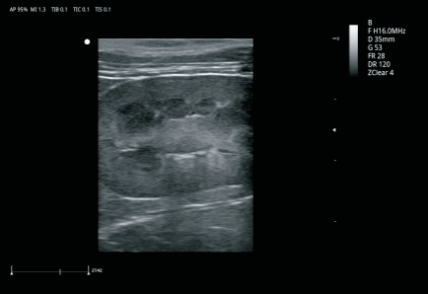

ZClear 自适应空域滤波技术

具有先进的自适应空域滤波,并与运动补偿时域滤波技术相结合,通过探测解剖结构边界位置有效降低斑点噪声,大幅增强组织边界显示能力和组织回声显示能力,增强临床诊断信心。

卓越的图像质量